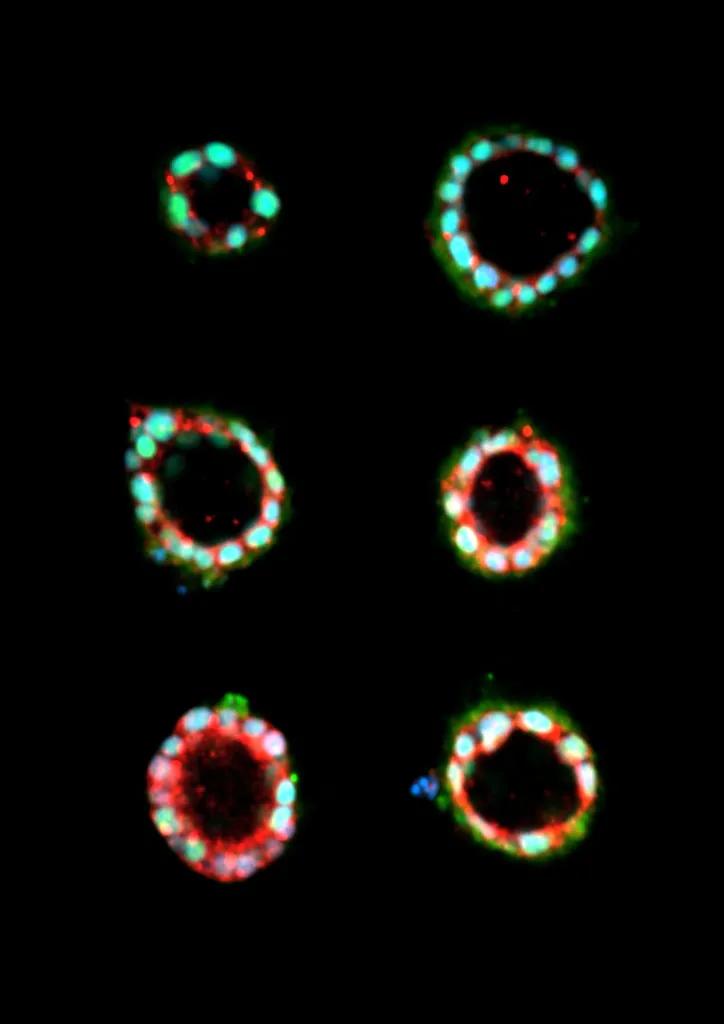

圖 | 干細胞組裝成類羊膜組織(來源:邵玥)

邵玥基于人類多能干細胞,實現(xiàn)了世界首例對著床期至原腸胚期的羊膜囊類胚胎的體外重建;通過微制造技術(shù),建立了著床期胚胎組織發(fā)育的藥物毒性篩查技術(shù)。通過與微流控器件的結(jié)合,完善了對著床期人類胚胎核心發(fā)育過程的體外再現(xiàn)。

圖 | 著床期人類胚胎羊膜囊(左,來自卡耐基收藏)與干細胞重建的類羊膜囊(右)(來源:邵玥)

“羊膜囊類胚胎芯片結(jié)合微流控系統(tǒng),實現(xiàn)了體外羊膜囊胚胎發(fā)育的可控。通過這項技術(shù)我們可以控制羊膜囊類胚胎的發(fā)育環(huán)境,在特定的時間和環(huán)境下給細胞增加適當(dāng)?shù)臈l件,就能高效獲得穩(wěn)定的結(jié)果,從而實現(xiàn)對人類胚胎多個早期發(fā)育過程的體外重建。利用機械微系統(tǒng)將干細胞在體外形成羊膜囊類胚胎做得更標(biāo)準(zhǔn)、更高效,在一定程度上將這個過程規(guī)范化和標(biāo)準(zhǔn)化?!?/p>